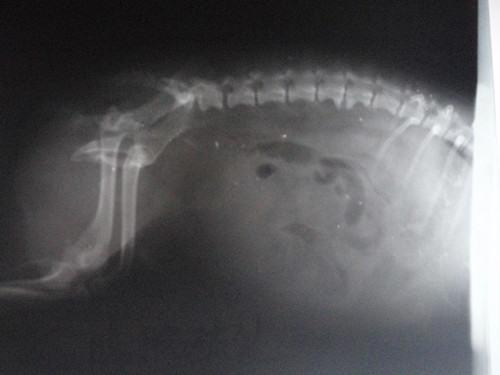

这是一例膀胱破裂的腹部影响,该犬来诊时已经是车祸第三天,初期无特殊异常,但这三天中一直未发现犬有排尿情况,就诊后发现,膀胱破裂,进行手术缝合及腹腔冲洗,预后良好。

犬膀胱破裂